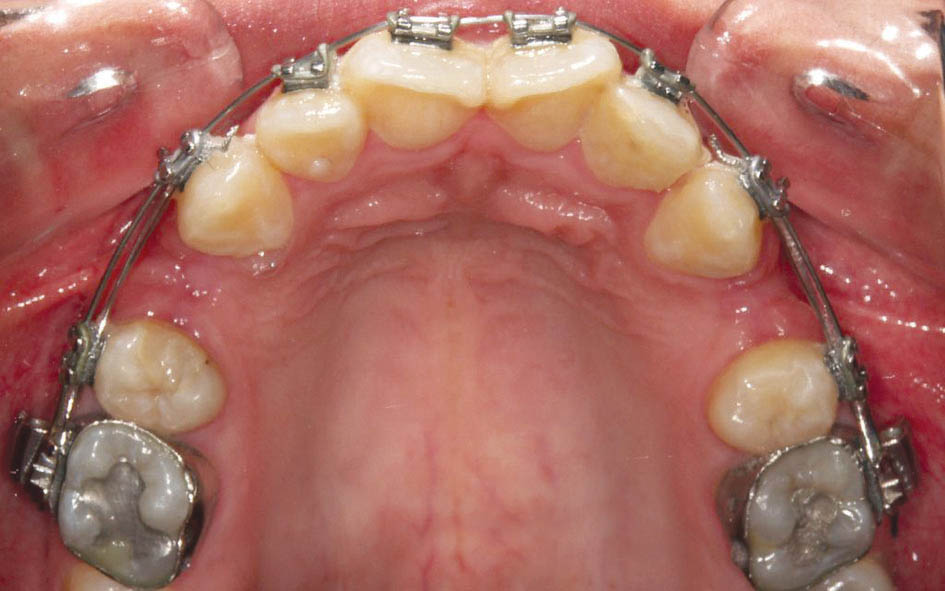

در شکل 1-3 دندانها مرتب هستند. براکت پرمولرها اشتباه چسبانده شدهاست، لذا بعد از قرار دادن سیم (شکل 2-3)، پرمولر اول که براکت آن ژنژیوالی است اکسترود و پرمولر دوم که براکت آن انسیزالی است اینترود شده و از قوس خارج گردیده است. به همین دلیل صحیح چسباندن براکتها برای مرتب شدن و هم سطح شدن دقیق دندانها بسیار مهم است.

شکل 2-3: ژنژیوالی چسباندن براکت منجر به اکسترود و انسیزالی چسباندن آن منجر به اینترود دندان میشود.